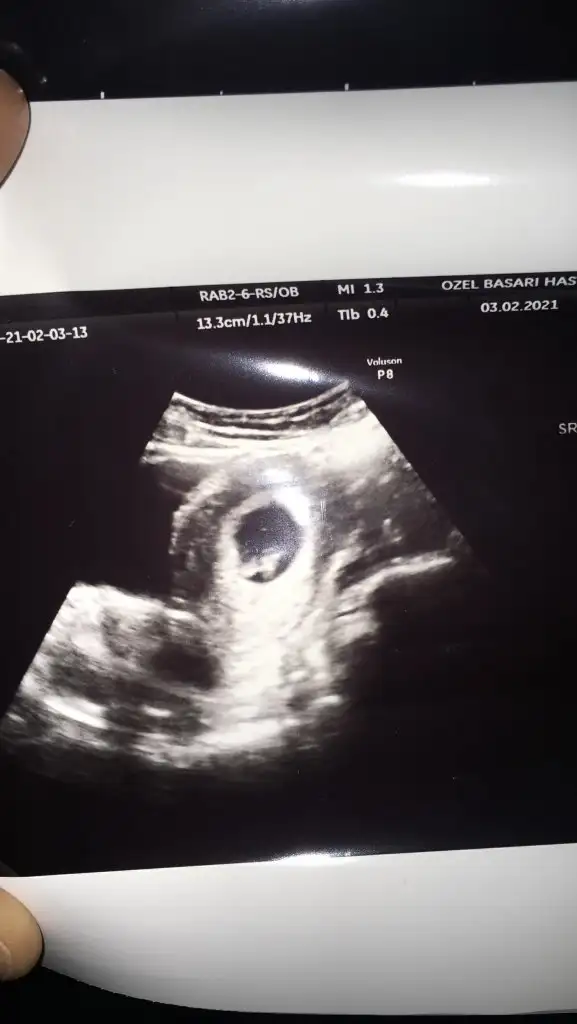

2 gün kala 31 ile öğrendim. 8 hafta bittiVesvese çok oluyor canım acaba kimyasal mi acaba dış gebelik mi bir sürü soru![]()

Endişelerimiz hiç bitmeyecek ama pozitif olalım, umarım her şey hepimiz için iyi ilerlerVesvese çok oluyor canım acaba kimyasal mi acaba dış gebelik mi bir sürü soru![]()

2 gün kala 31 ile öğrendim. 8 hafta bittigönlüne göre olsun sağlıcakla gelsin inşallah

Endişelerimiz hiç bitmeyecek ama pozitif olalım, umarım her şey hepimiz için iyi ilerler![]()

Canım bence kız

Canım bana erkek gibi geldiBide anlayan arkadaslard rica etsem cinsiyet tahmini yapabilir mi nütfeen nütfeen

Eki Görüntüle 2775718